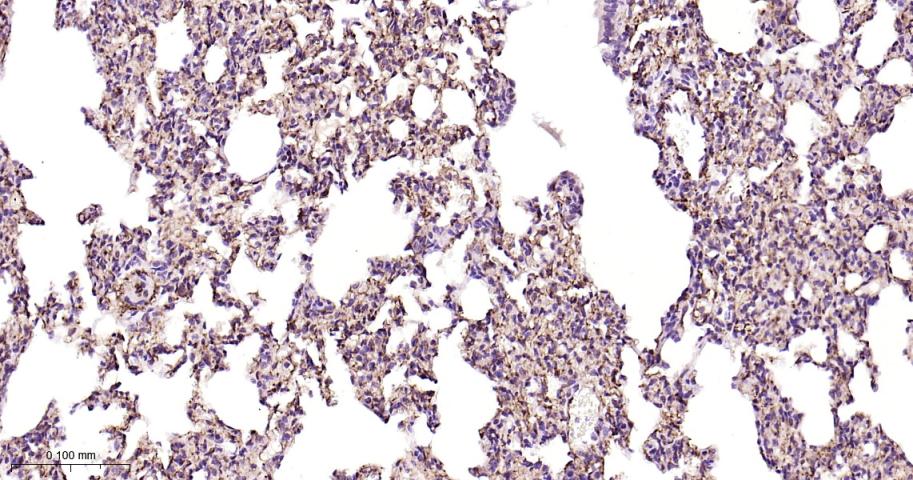

Paraformaldehyde-fixed, paraffin embedded Human Lung Cancer; Antigen retrieval by boiling in sodium citrate buffer (pH6.0) for 15 min; Antibody incubation with CD146 Monoclonal Antibody, Unconjugated(bsm-61136R) at 1:200 overnight at 4°C, followed by conjugation to the bs-0295G-HRP and DAB (C-0010) staining.